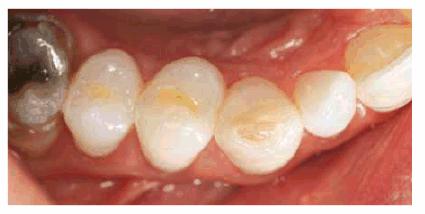

Figure 16-8A and B: Gray stain on lateral incisor (A) is a result of an amalgam restoration on the lingual surface of the tooth (B).